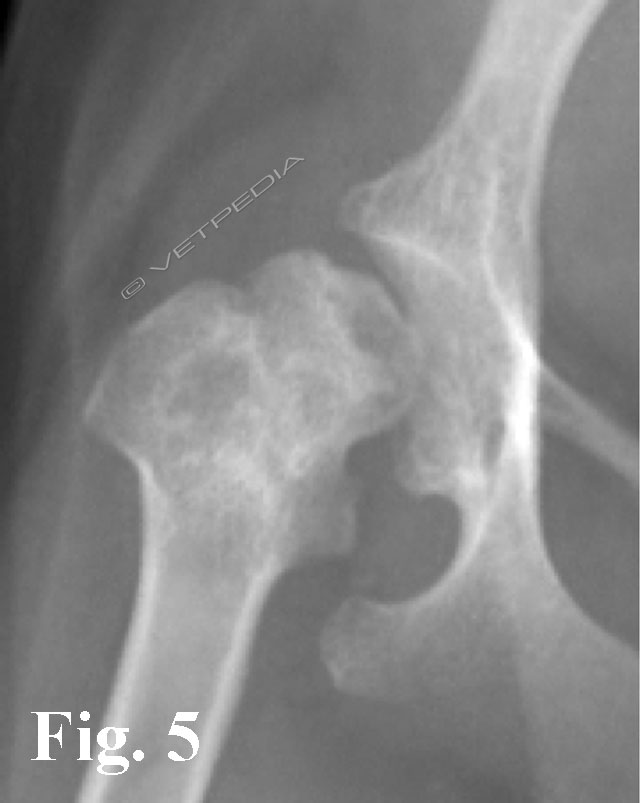

{{/_source.additionalInfo}}La necrosi asettica della testa del femore è anche denominata malattia di Legg Calvè Perthes e necrosi avascolare della testa del femore. Si tratta di un'affezione ortopedica coinvolgente l’articolazione coxofemorale di cani di razza toy o di piccola taglia durante il periodo dell’accrescimento, ad interessamento più frequentemente monola